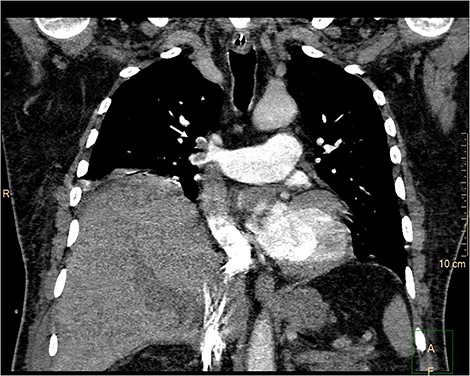

Upper abdominal magnetic resonance imaging, magnetic resonance cholangiopancreatography (Fig. 1) and contrast-enhanced computed tomography (CT) (Fig. 2) revealed large walled-off pancreatic necrosis in the pancreatic head, measuring 10.5 × 6.5 × 9 cm, compressing the inferior vena cava, the common bile duct and the duodenum. There were also peripancreatic pseudocysts, with the biggest measuring at 12.5 cm.

Contrast-enhanced CT. Large walled-off pancreatic necrosis in the pancreatic head, pressing inferior vena cava and duodenum (white arrow).